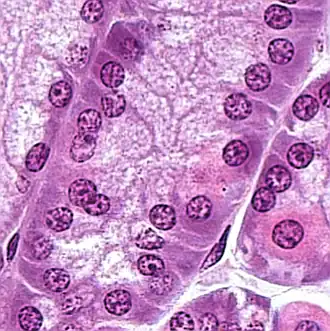

Een maaghoofdcel, peptische cel of hoofdcel (exocrinocytus principalis) is een type maagkliercel in de maag, die pepsinogeen en maaglipase vrijgeeft. Het is de cel die verantwoordelijk is voor de secretie van chymosine bij herkauwers en sommige andere dieren.[1] De cel kleurt basofiel bij H&E-kleuring vanwege het grote aandeel ruw endoplasmatisch reticulum in het cytoplasma. Maaghoofdcellen bevinden zich over het algemeen diep in het maagslijmvlies, in de fundus en maagwand.[2][3] De fundus is de koepel van de maag (de fundus gastricus).